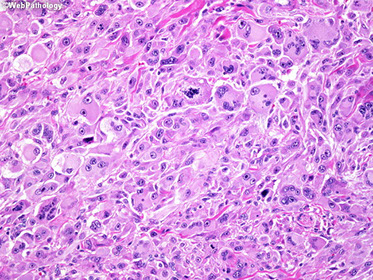

Clear cell sarcoma (CCS)

aka melanoma of soft parts

Rare aggressive, yet slowly progressing tumor seen in young adults (avg 30 yo), M>F in deep tissue of foot and ankle (esp near tendons or aponeuroses)

Gross: firm, well-circumscribed with gritty texture under the scalpel

- avg 4 cm, variable necrosis

Micro: Nested cells separated by thin fibrous septae c spindle, epithelioid and floret-like MNGCs

- frequently c melanin (2/3) and rhabdoid cells (pleomorphic) and necrosis and mits

- can have wreath-like giant cells

Cyto: variable cellularity, can have microacinar structures that look like adenoca

IHC: (+) S100, HMB45, micropthalmic transcription factor, MelanA, iron

- negative alpha SMA, desmin, CAM5.2

Genes: t(12;22)(q13;q12) R1 (ATF1) and EWS (negative in melanoma) making EWS-R1 (ATF1) (also seen in angiomatoid fibrous histiocytoma)

Tx: excision

Px: 5 yr survival 2/3; size most important factor

- freq recurrence, mets to nodes and distantly

Clear cell sarcoma

Touton-like giant cell in clear cell sarcoma